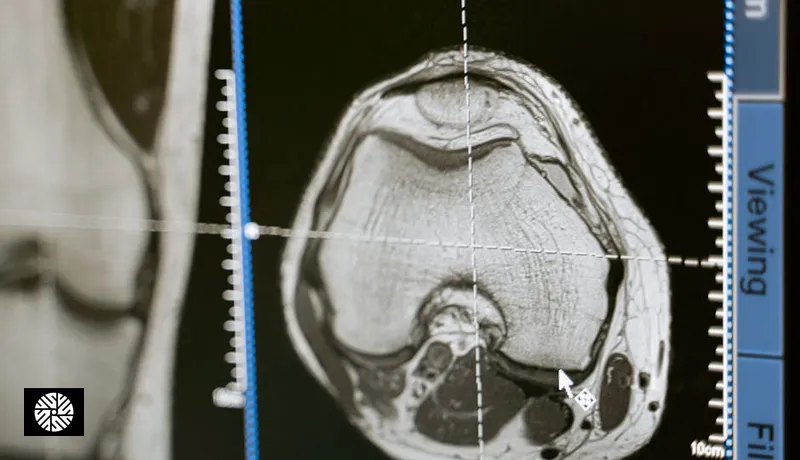

The Taiwan number is not a typo. Our partner hospitals operate at a different cost basis — public-sector subsidies on imaging equipment, lower medical malpractice insurance, and a different physician reimbursement model. The clinical protocol is the same: 3 Tesla MRI scanner (Siemens MAGNETOM Vida or equivalent), board-certified radiologist read, English-language report. For a deeper technical look at the hardware itself, see Taiwan's 3T MRI technology sets the standard in Asia.

4. Technique — scanner make/model (e.g., Siemens MAGNETOM Vida 3T), sequences acquired (T1, T2, DWI, ADC, T2 FLAIR), contrast administration if any, slice thickness.